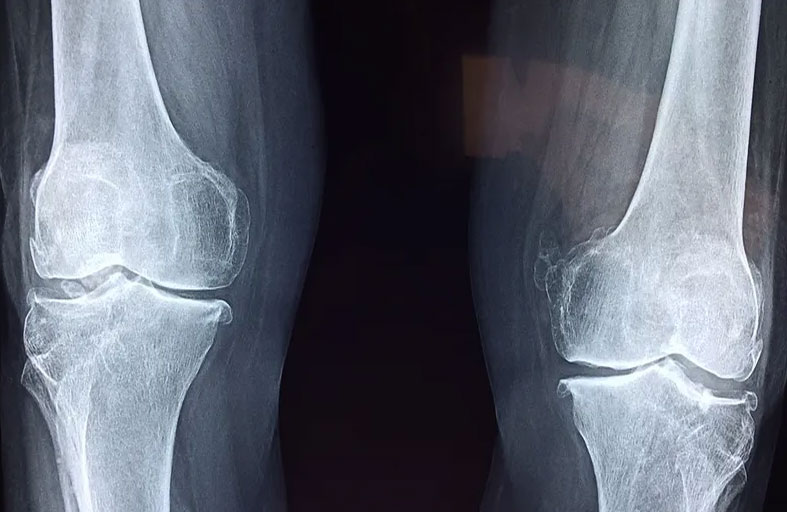

لا تختلف الأبحاث على أهمية الرياضة وما تحققه من نتائج صحية مذهلة، لكن أنواعها ليست متساوية عندما يتعلق الأمر بالعظام والحفاظ عليها سليمة.

يشير بحث جديد، نشر بمجلة " ميديسن آند ساينس"، إلى أن الأطفال سوف يتمتعون بصحة أفضل إذا شاركوا في رياضات متعددة الاتجاهات مثل كرة القدم أو كرة السلة، بدلاً من الأنشطة أحادية الاتجاه مثل الجري.

وقال مؤلف الدراسة ستيوارت واردن: "تُظهر البيانات أن ممارسة الرياضات متعددة الاتجاهات، يقلل من خطر إصابة الشخص بأمراض العظام من خلال تطوير هيكل عظمي أكبر وأقوى".

ووجد الباحثون أن النساء اللواتي شاركن في كل من رياضة الجري والرياضات متعددة الاتجاهات عندما كن أصغر سناً كان لديهن قوة عظام أكبر بنسبة 10 بالمئة إلى 20 بالمئة مقارنة بنظيراتهن اللاتي ركضن فقط.

بالإضافة إلى ذلك، أظهر المسح أن أولئك الذين مارسوا رياضات مثل كرة القدم أو كرة السلة عندما كانوا أصغر سناً يتمتعون ببنية عظام وقوة أفضل من أولئك الذين كانوا يجرون فقط أو يسبحون أو يركبون الدراجات.